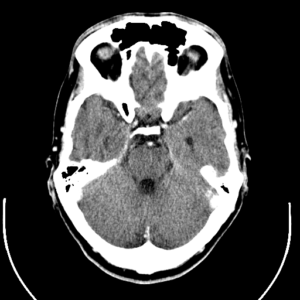

At Qrons, researchers integrate 3D printable custom scaffolds with innovative, engineered mesenchymal stem cells (MSC) for brain damage, and use a multidisciplinary approach to treat this highly complex disease to regenerate patients. Damaged organization. The company suggested that these genetically modified MSCs provide a mechanism for secreting a continuous stream of neuroprotective agents and nerve regeneration agents to drive the TBI repair mechanism. These drugs can prevent further neuronal damage and have the potential to stimulate neurons to migrate to the damaged site, regenerate axons and regenerate brain tissue.

Qrons already has two candidate products for the treatment of TBI, both of which integrate proprietary, modified MSC and smart synthetic materials. QS100 is a damage-specific3D printingYes, implantable MSCs synthetic hydrogel for the treatment of penetrating brain injury, while QS200 is an injectable MSCs synthetic hydrogel for the treatment of diffuse injuries (commonly called concussion).